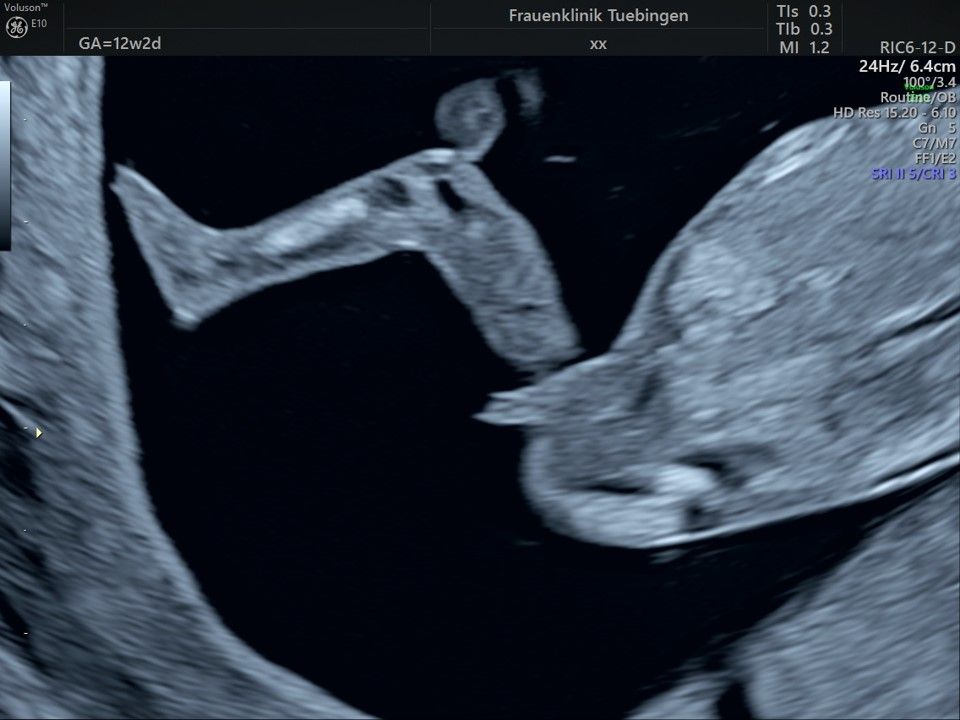

Bauchwanddefekt

Es sollte berücksichtigt werden, dass strukturelle/anatomische Fehlbildungen (z.B. angeborene Herzfehler) deutlich häufiger auftreten. Bei etwa 2-3% (1:30 - 1:50) der Feten werden Fehlbildungen gefunden. Diese können isoliert, d.h. ohne Chromosomenstörung auftreten. Sie werden aber gehäuft bei Trisomien und andersartigen Veränderung des Erbguts gefunden. Daher ist eine detaillierte Ultraschalluntersuchung im Rahmen der Risikobeurteilung unerlässlich. Sollte eine Fehlbildung erkannt werden, so ist eine Risikoberechnung für Trisomie 21 alleine nicht ausreichend. Hier sollte eher an eine Fruchtwasser- oder Mutterkuchenpunktion gedacht werden, um eine Chromosomenstörung erkennen oder ausschließen zu können.